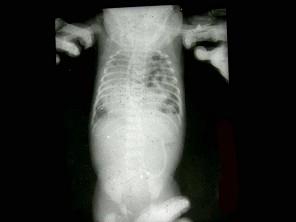

问题 男,15天,进食呕吐5天、呼吸困难2天,如图所示,最可能的诊断为?(?)

选项 A.先天性肺气肿 B.左侧膈疝 C.右位心 D.右侧肺不张 E.右肺发育不全

答案 B